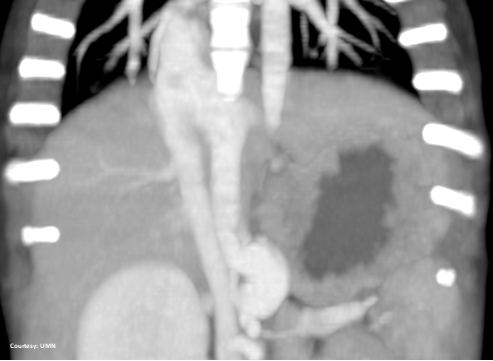

“LGHV +PancV -GSV”

Left Gastric – Left Hepatic Vein Shunt with Pancreatic Vein contribution and absent Gastrosplenic Vein